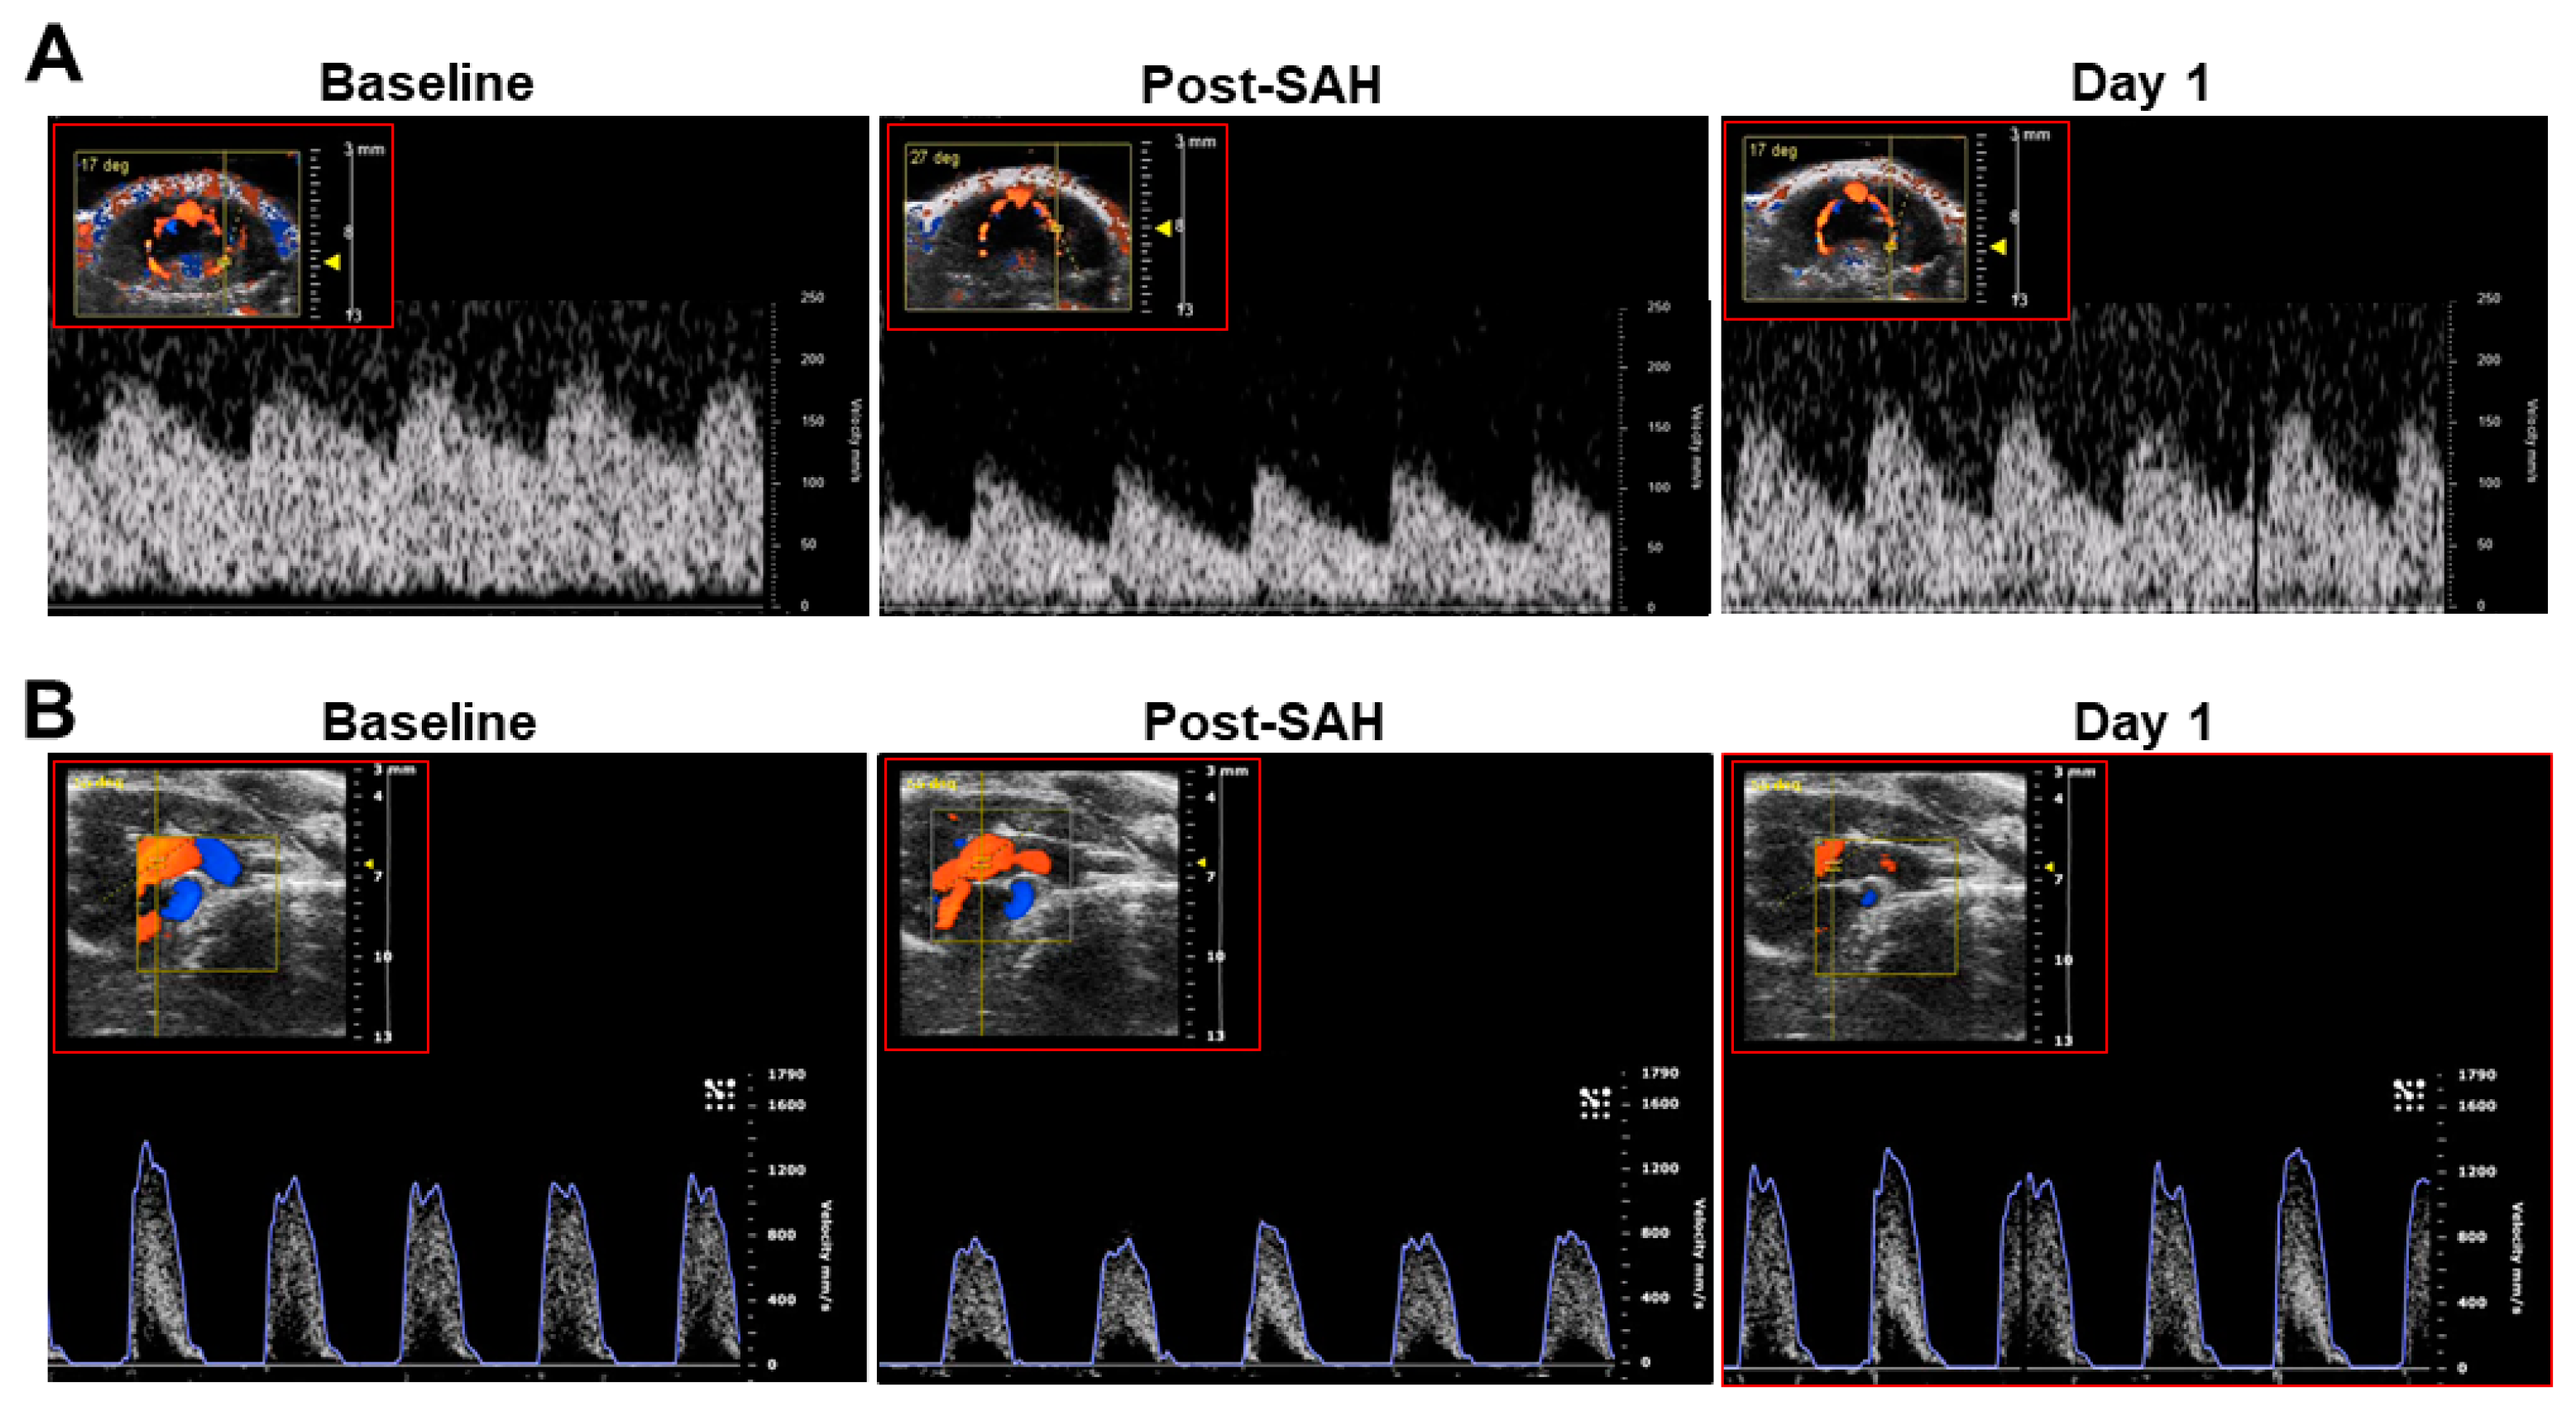

In the original publication [1], there was a mistake in Figure S2 as published. A representative recording of the transcranial Doppler flow velocity tracing in the right panel of (A) was incorrectly placed due to unexpected technical error of the offline data output system. The corrected Figure S2 appears below.

Figure S2. Representative images of flow velocities of the left middle cerebral artery (A) and left ventricular outflow tract (B) in mice before (baseline), immediately after SAH, and 24 h (day 1) after experimental SAH in a mouse treated with neurotropin after SAH induction.